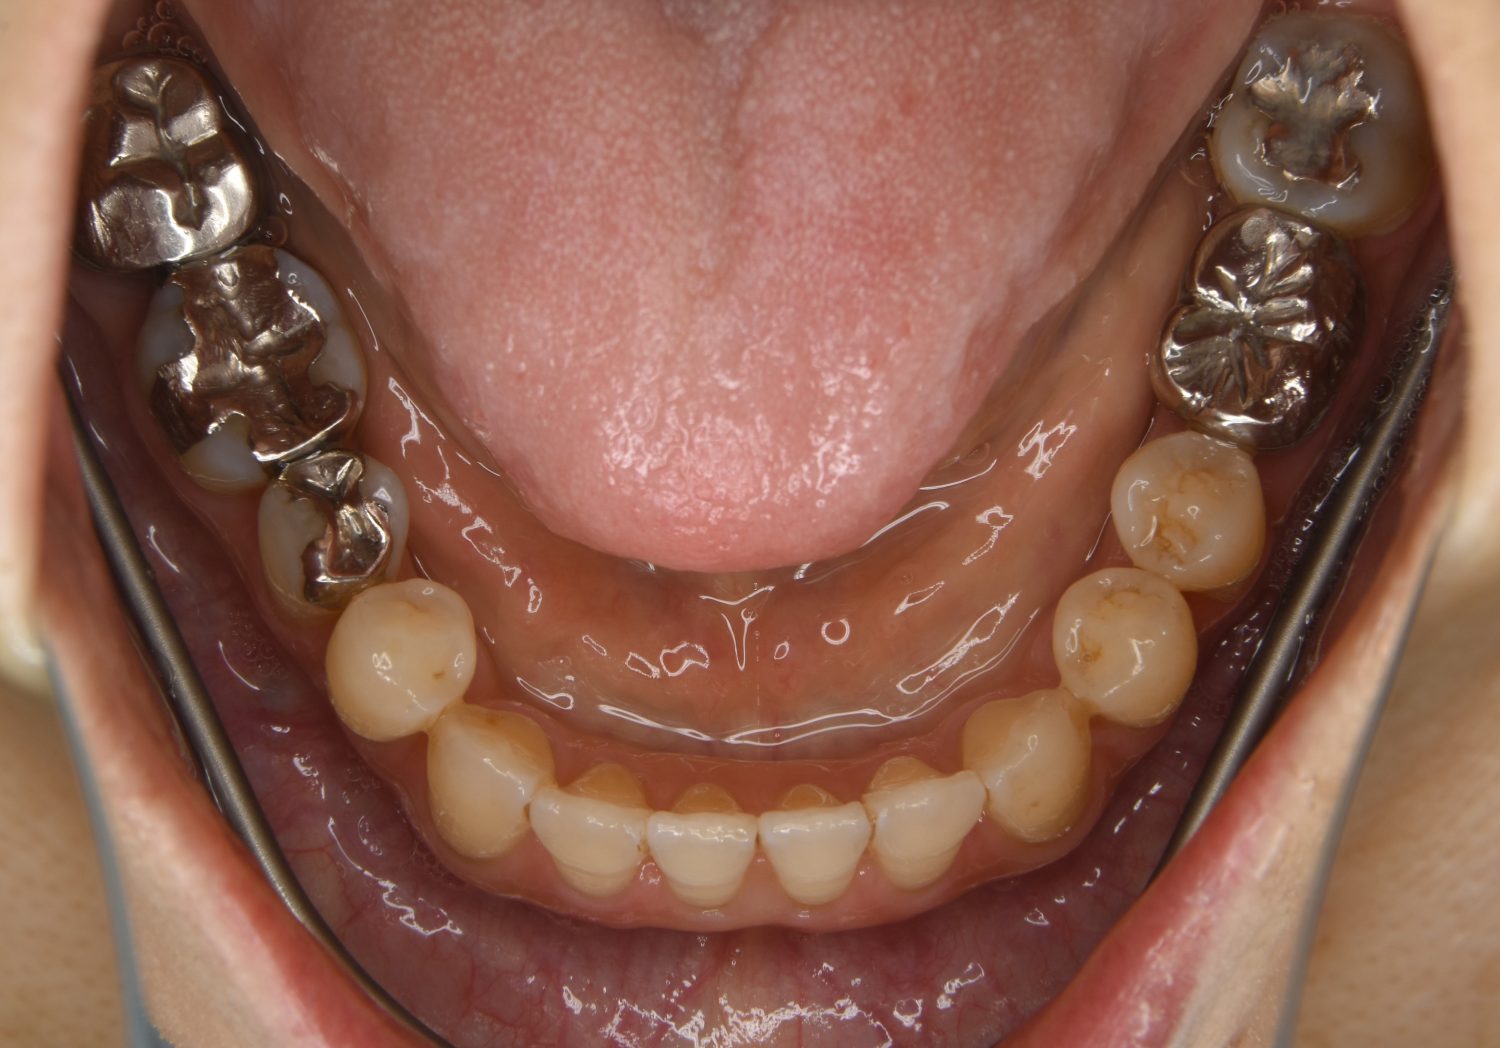

叢生の症例紹介②

Before

After

主訴

歯の凸凹を治したい。

治療内容

アライナー(インビザライン)にて非抜歯で治療を行いました。

上下前歯部に叢生(凸凹)が認められる状態でした。歯列の遠心移動を行うことで機能面および審美面が改善されました。